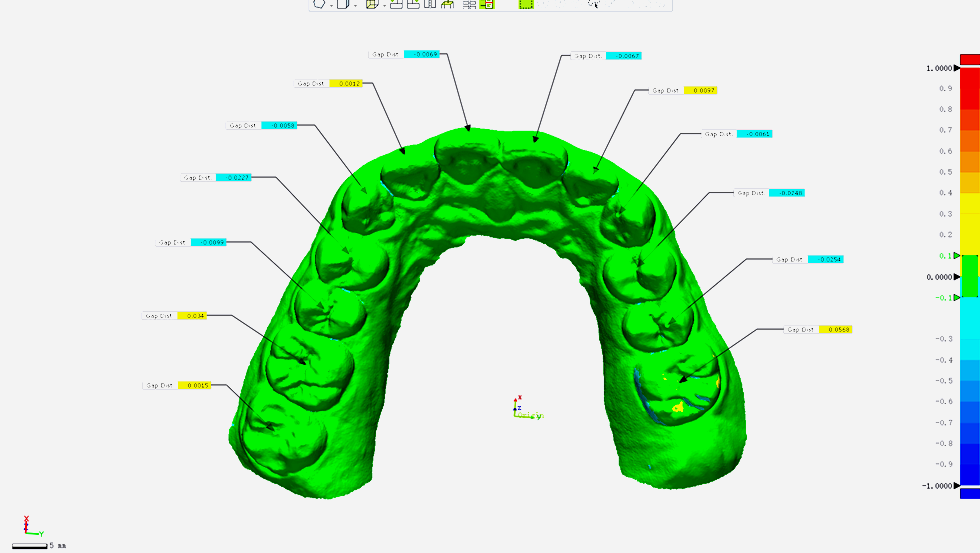

0.01mm

準中更準

優化軟件算法及硬件成像機制,Aoralscan 3精度優化超過30%,與模型掃描儀精度比對?≤0.01mm.*